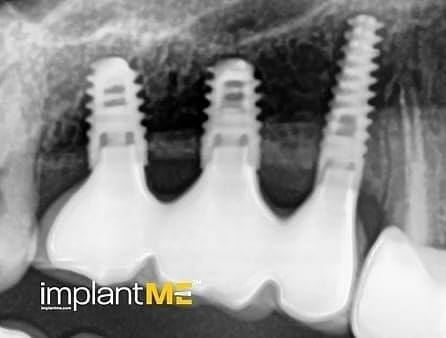

Атрактивните и особено здравите заби не се само одлучувачки дел од нашиот изглед, туку и на нашата личност. Во минатото, губењето на еден или повеќе заби имаше одлучувачка улога врз изгледот на луѓето. Поради модерната орална имплантологија, ова повеќе не е случај. Со релативно мали процедури за орална хирургија, индивидуалните или сите непостоечки заби можат да бидат заменети со импланти, естетски и функционално еднакви на природните заби. Преку вметнување импланти во форма на корен, можно е да се избегнат промени на соседните заби и да се зацврстат коронки што тешко може да се разликуваат од вистински заби во празнините на забите. Коронките или мостовите поддржани од импланти се прицврстени на колец зацврстен во коска, што им дава на пациентите џвакање со чувство скоро нималку различно од нивните заби. Во случај на потполна беззабост, имплантите може да претставуваат сигурна потпора за мобилна протеза, како и за големи фиксни мостови.

Забната протетика поддржана од имплант тесно се доближува до природните заби. Коронките водат со нивниот природен изглед, имплантите со нивната стабилност, а двете заедно со нивното позитивно влијание врз функционалното зачувување на целиот мастикаторен апарат.